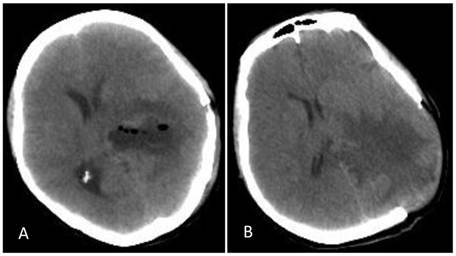

A 46-year-old female was admitted to the hospital due to a sudden onset of headache that had lasted for 5 hours. Physical examination showed neck stiffness and Kernig's sign but no other positive signs of the nervous system. Computed tomography (CT) showed a high-density space-occupying lesion in the trigone of the left lateral ventricle. Hemorrhage surrounded the lesion and formed a hematoma, which extended forward into the contralateral ventricle and affected the third and fourth ventricles (Figure 1). Computed tomography angiography (CTA) showed no intracranial artery malformation. The medial blood vessels of the lesion in the trigone of the lateral ventricle were disordered, and the lesion was supplied by anterior and posterior choroidal arteries. Maximum intensity projection clearly revealed a high-density calcification shadow at the rear of the lesion, and the surrounding brain tissues were mildly compressed (Figure 2). Magnetic resonance imaging (MRI) showed that the area of the lesion was 2.86 cm × 2.68 cm with mixed T1WI and T2WI signals. The lesion was heterogeneous in density, and its center was cystic. Slightly high abnormal T1WI and T2WI signals were noted in the bilateral lateral ventricles, and fluid was visible in the occipital horn of the left lateral ventricle (Figure 3).

Figure 1

CT at the time of onset of intraventricular hemorrhage. A-B: A space-occupying lesion in the trigone of the left lateral ventricle was observed; it had a low-density cystic shadow in the middle (arrow). A high-density calcification shadow was detected at the rear of the lesion, and the surrounding brain tissues were mildly compressed. C: Hemorrhage surrounded the lesion and formed a hematoma, which extended forward into the lateral ventricle, and the hemorrhage affected the third ventricle (arrow). D: The hemorrhage also affected the fourth ventricle (arrow).